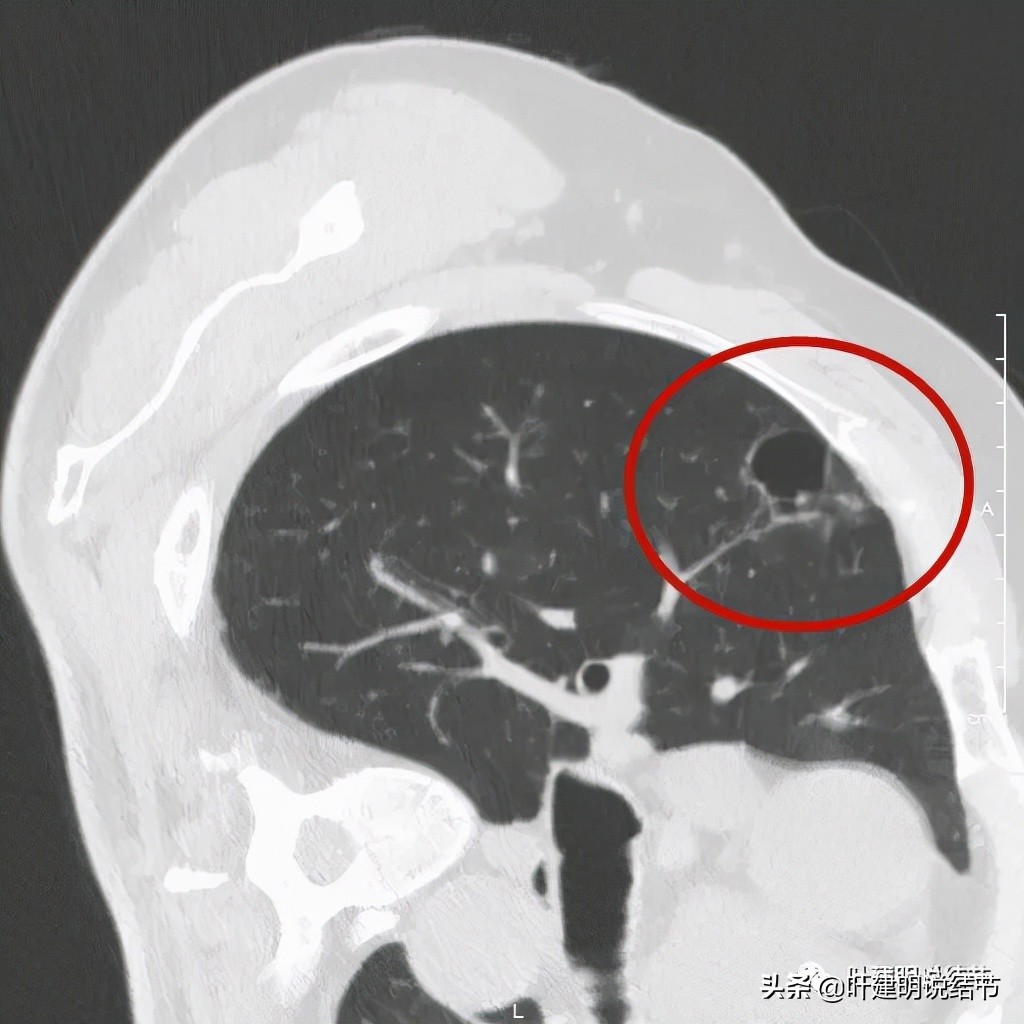

以上诸图是病灶4:考虑囊腔型肺癌可能性大,壁厚薄不均,内壁不光滑,有血管进入病灶,有少许密度偏高的成分,但纵隔窗上未见,不是真正意义上的实性成分。